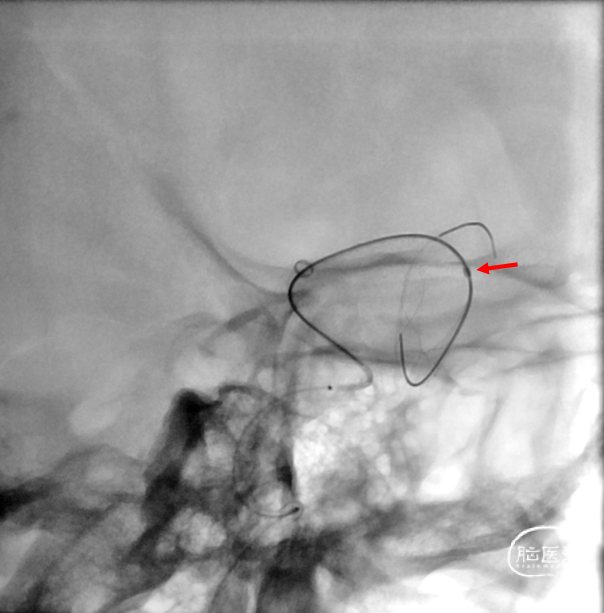

nuva 4/40

支架打开不良

支架重新打开良好

2、本案例大脑中动脉起始部极重度狭窄是FD治疗的难点,支架导管通过困难、支架打开困难。

3、大脑中远端、中段、开口和颈内动脉末端血管变径很大,支架的长度也会发生很大变化。

4、展望:血流导向装置治疗未破裂的大脑中动脉大型夹层动脉瘤是可行的和安全的,但在弯曲段及合并狭窄的血管条件下,支架打开困难、贴壁不良和扭结是面临的主要技术难题,结合球囊扩张可以辅助支架更好的释放。术前术后多模态、多维度的评估以及密切的随访是必要的。